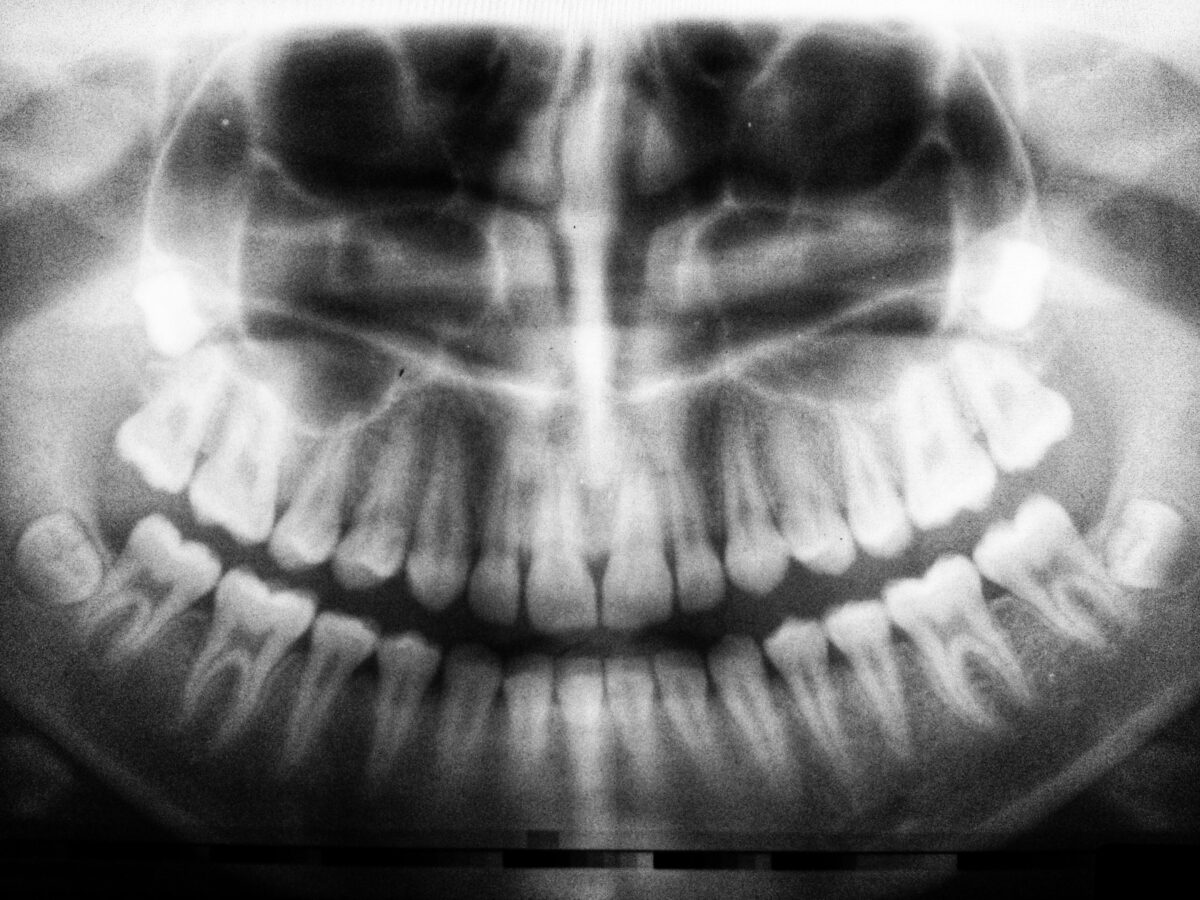

Przez całe życie towarzyszy nam świadomość, że zęby się nie regenerują. W dzieciństwie wypadają mleczaki, ustępując miejsca stałemu uzębieniu, które ma służyć do końca życia. Jeśli z jakiegoś powodu tracimy ząb, jedynym rozwiązaniem jest dziś implant, most lub proteza. Ale czy tak będzie zawsze?

Japońscy naukowcy pracują nad lekiem, który może całkowicie zmienić to, jak rozumiemy medycynę regeneracyjną w kontekście uzębienia. W 2024 roku rozpoczęli pierwsze badania kliniczne z udziałem ludzi, a ich celem jest umożliwienie naturalnego odrastania utraconych zębów. Jeśli wszystko pójdzie zgodnie z planem, już w 2030 roku lek może trafić do użytku klinicznego.